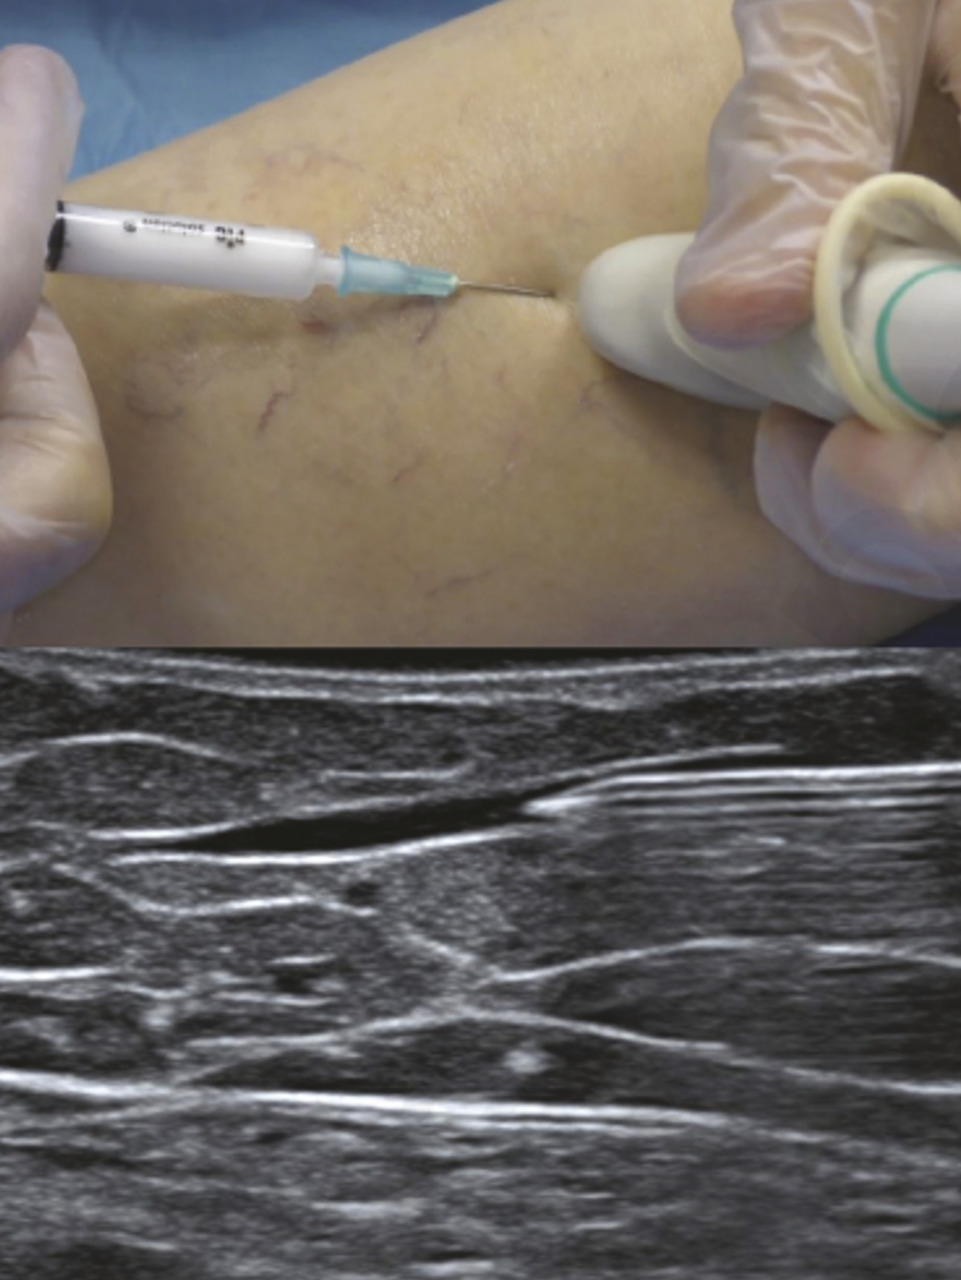

Sclérothérapie sous contrôle échographique

En cas de varices plus profondes, non visibles ou bien dès lors que le guidage échographique est possible, l’utilisation de ce dernier est recommandée. On parle d’échosclérothérapie.

Ses indications sont les suivantes :1 troncs saphènes, perforantes, récidives post-chirurgicales, régions à risque telles que la région inguinale ou la fosse poplitée. Les sondes d’échographie étant de plus en plus performantes, on peut également scléroser une veine réticulaire d’alimentation par exemple de quelques millimètres de diamètre (fig. 4).